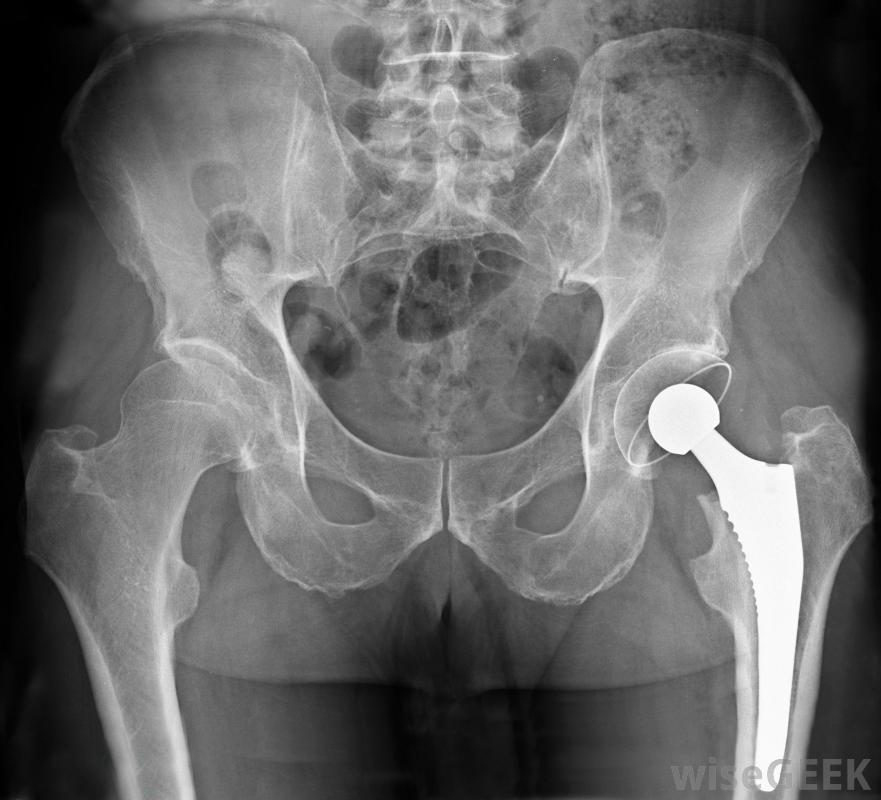

關節炎是一種引起關節炎的疾病。身體的一個或多個關節可能會受到影響。髖關節炎是髖關節的炎癥。髖關節連接骨盆骨和大腿。最常見的髖關節炎是骨關節炎一個健康的髖關節和一個患有骨關節炎的人。關節的磨損似乎是原因。髖關節炎影響某些人而不是其他人的原因并不確切很清楚。然而,某些危險因素與關節炎的發生有關。例如,患有其他疾病的人,如狼瘡,可能有患髖關節炎的風險。超重也可能是導致這種情況的一個因素。盡管它可能發生在任何年齡段,但髖關節炎通常發生在第六個年齡段有幾種不同的藥物可以用來治療疼痛和炎癥髖關節炎的主要癥狀是疼痛。疼痛不僅出現在髖關節,而且可能會輻射到大腿前部。疼痛可能只出現在活動中,如步行,或可能一直發生。活動范圍也可能受到影響嚴重的髖關節炎患者可能需要髖關節置換術。診斷通常是在體檢和可能的x光檢查后作出的。醫生將確定活動范圍并尋找僵硬和詢問疼痛。早期診斷很重要,因為它可以開始治療并減緩病情的進展。髖關節炎會導致疼痛、僵硬和執行困難最簡單的任務,包括步行。治療將取決于關節炎的嚴重程度及其對生活方式的影響。輕微的髖關節炎可以通過營養補充劑、改變生活方式和物理療法。超重者可建議減肥。在運動或運動中過度使用髖關節的人,可能建議改變活動。在某些情況下,營養補充劑可能會有所幫助。葡萄糖胺和軟骨素都是補充劑,被認為有助于減緩關節損傷,并有可能促進新的軟骨發育在你開始服用補充劑之前,最好咨詢一下你的醫生藥物治療也有助于減輕關節炎引起的疼痛。消炎藥,如布洛芬,可能會有幫助。如果非處方藥沒有幫助,更強烈的疼痛和抗炎藥可能需要醫生開如果其他治療方法不起作用,且癥狀嚴重,則可能需要進行髖關節置換手術。髖關節置換手術分為部分置換術和完全置換術兩種。如果髖關節損傷嚴重,則可能需要進行全髖關節置換術疼痛是髖關節炎的主要癥狀。